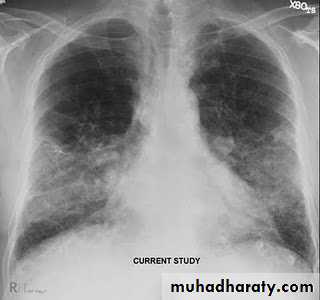

Radiology

Chest X-ray: typically small lung volumes with reticulonodular shadowing

HRCT: reticulonodular shadowing in early stage and honeycomb cysts and traction bronchiectasis in advance stage.

Abnormal chest X-ray at presentation with lower zone bi-basal reticular and reticulonodular opacities. 'honeycomb' appearance in advanced disease.

HRCT may be diagnostic, demonstrating a patchy, predominantly peripheral, subpleural and basal reticular pattern with subpleural cysts (honeycombing).